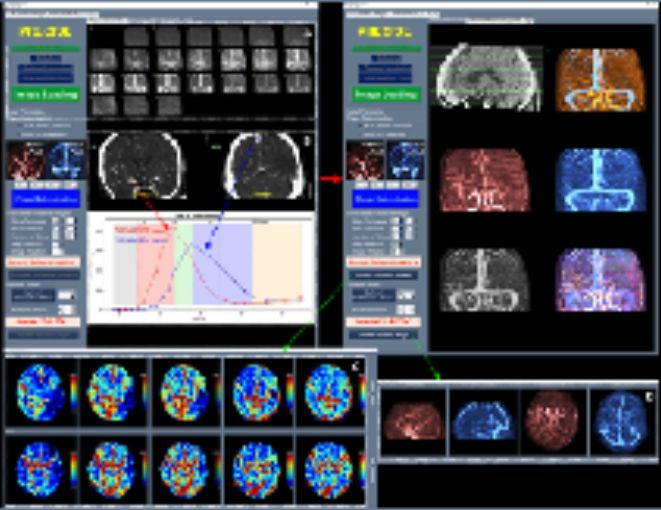

적용 기술별로 살펴보면, 인공지능(AI) 기술을 활용한 의료기기가 연구·개발 전반에서 가장 활발히 활용되고 있는 것으로 나타났다. 2024년에는 AI 기반 혁신의료기기가 15개였으나, 2025년에는 25개로 증가했다.

특히 2025년에는 생성형 AI 기술을 활용한 의료기기가 혁신의료기기로 처음 지정됐다. 해당 제품은 흉부 X-ray 영상을 분석한 뒤 42종의 흉부 질환 및 영상 의학적 소견에 대한 판독 소견서(초안)를 자동 생성하여, 영상의학과 전문의의 진단 결정을 보조하는 의료기기이다.

이와 함께 허혈성 뇌혈관 질환 환자를 대상으로 혈관재개통 치료가 필요한 환자 선별을 지원하는 소프트웨어 등 다양한 진단·치료 보조 AI 의료기기들이 혁신의료기기로 지정됐다.